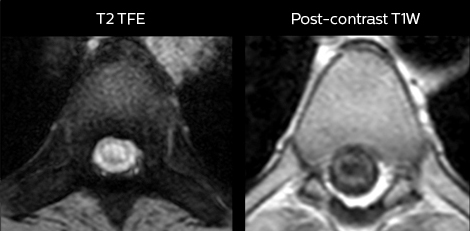

“For the thoracic and cervical spine routine non-contrast exam, for example, we perform one mDIXON T2 TSE sequence, which provides us with two outputs: the fat-and-water-together T2-weighted images, as well as the water-only sagittal T2-weighted images. And then we also perform an axial gradient echo exam.”

Cervical spine routine exam

This patient presented with headache that was worse with neck flexion and we see a Chiari 1 malformation with low-lying cerebellar tonsils as well as some degenerative cervical thrombolytic change.